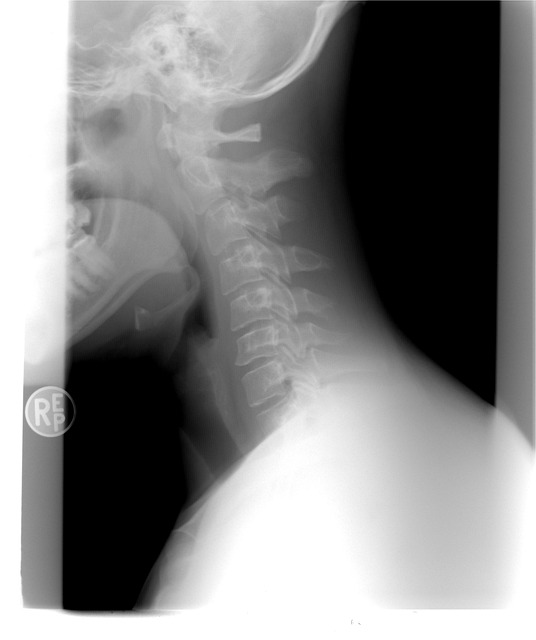

손목의 손목터널을 지나가는 정중신경이 압박을 받아 발생하며, 주로 엄지, 검지, 중지에서 저림 증상이 나타납니다. 밤에 증상과 통증이 심해지는 경향이 있습니다. - 목 디스크(경추 신경병증)에 의한 말초신경 압박

컴퓨터 작업이나 스마트폰 사용이 많을 때 손저림 증상의 발병 위험이 높은 원인으로 목뼈 사이의 디스크가 신경을 눌러 발생합니다. 손과 팔, 어깨까지도 저림 증상을 유발합니다. - 팔꿈치터널증후군(주관증후군)에 의한 말초신경 압박